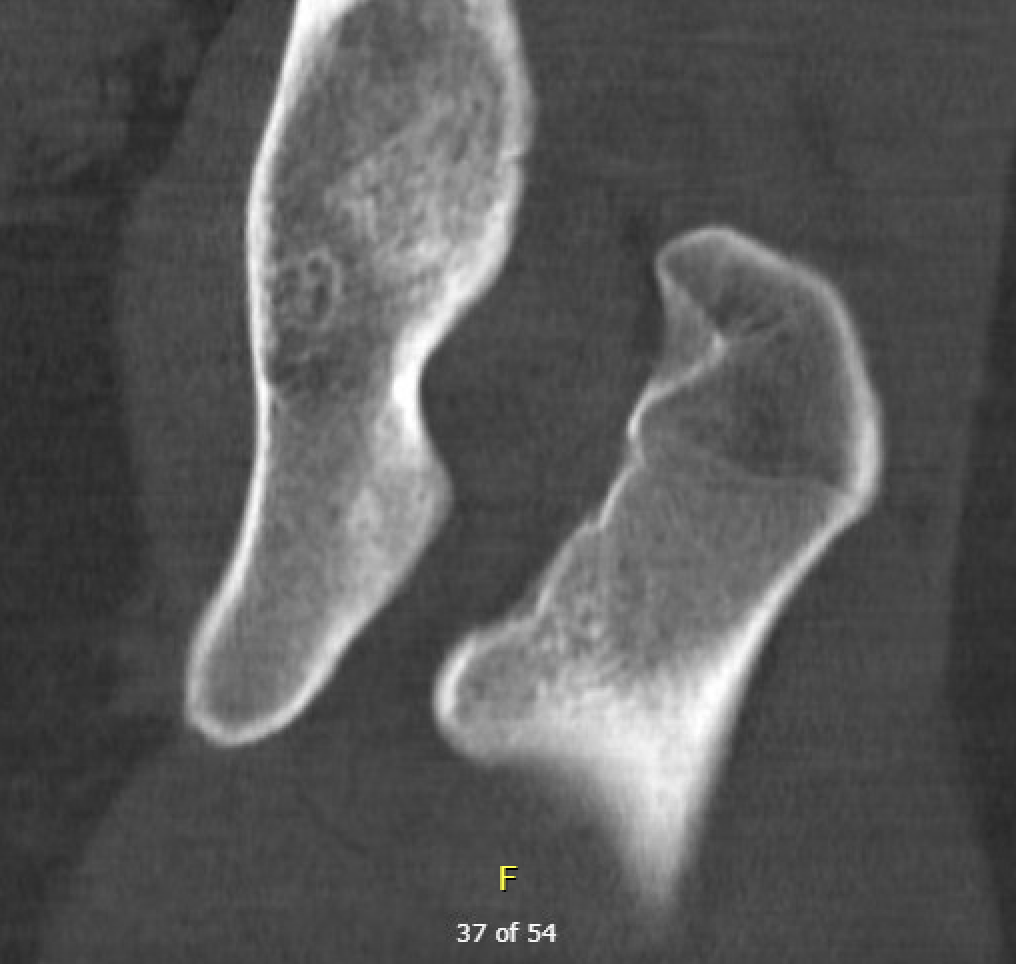

Reduced ischiofemoral space - distance between the lesser trochanter and the ischial tuberosity

Reduced quadratus femoris space - distance between hamstring tendon and iliopsoas

Inflammation / edema in quadratus femoris +/- fatty degeneration

CT